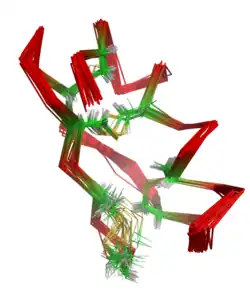

Maurotoxin is a peptide of 34 amino acids (sequence VSCTGSKDCYAPCRKQTGCPNAKCINKSCKCYGC) cross-linked by four disulfide bridges (Cys3-Cys24, Cys9-Cys29, Cys13-Cys19, Cys31-Cys34), with an atypical pattern of organization compared with other scorpion toxins; this unusual pairing of cysteine residues may be mediated by the presence of adjacent prolines. The peptide contains an alpha helix linked by two disulfide bridges to a two-stranded antiparallel beta sheet.